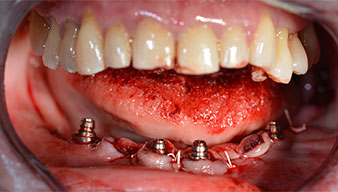

Направи се скенер с триизмерна компютърна томография (CBCT, Planmeca), за да се подпомогне планирането и да се намалят рисковете. Той показа, че качеството и количеството на наличната кост са достатъчни за операцията и имедиатното възстановяване, използвайки Fast & Fixed метод. Следвайки протокола за тази концепция, имплантите са поставени на 35, 32, 42 и 45 позиция. Ангулирането на дисталните импланти до 45° промени профила в задната зона и осигури по-голяма поддръжка в многоъгълната зона (Фиг. 3).

След отстраняване на частичното обеззъбяване в долната челюст, алвеоларният гребен е разкрит от 37 до 47.

Изходът на долночелюстния нерв е първоначално идентифициран като ограничена анатомична структура и, след това, кортикалната кост на гребена е загладена с прав наконечник и голям борер с розовиден профил (Фиг. 4).

Ангулираните абатмънти (35°) са завити в имплантите, за да компенсират отклонението от дисталните импланти, така че в резултат профилът на разположение на всички импланти да е възможно най-перпендикулярен на нивото на захапката. Това е предпоставка за оклузално поставяне на временна и впоследствие на постоянна протеза (Фиг. 15 и 16).

Светлината увеличава контраста в оралната кухина и подобрява визуалното възприятие. Обратният наконечник и S-11 прав наконечник на W&H са с външно охлаждане, което е голямо предимство по отношение на физиологичния разтвор, който достига точно, където трябва и може да бъде впоследствие редуциран, ако е необходимо. Правите и обратни наконечници могат да бъдат разглобени, което е силно препоръчително от гледна точка на хигиената и стерилизацията. Поставени са четири импланта SKY с размери 4.0 x 14 мм.